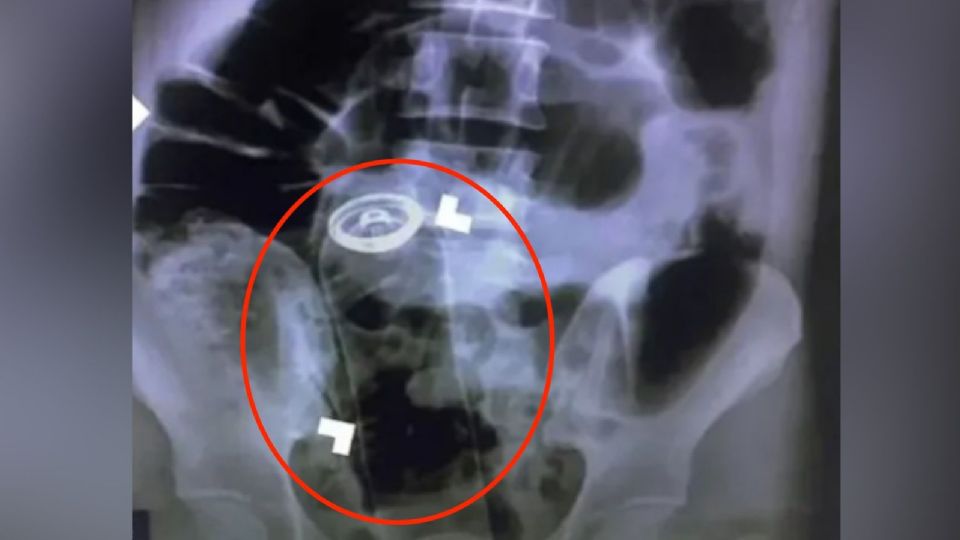

Hombre pensó que estaba estreñido y terminó en el hospital: le hallaron un desodorante atorado en el recto